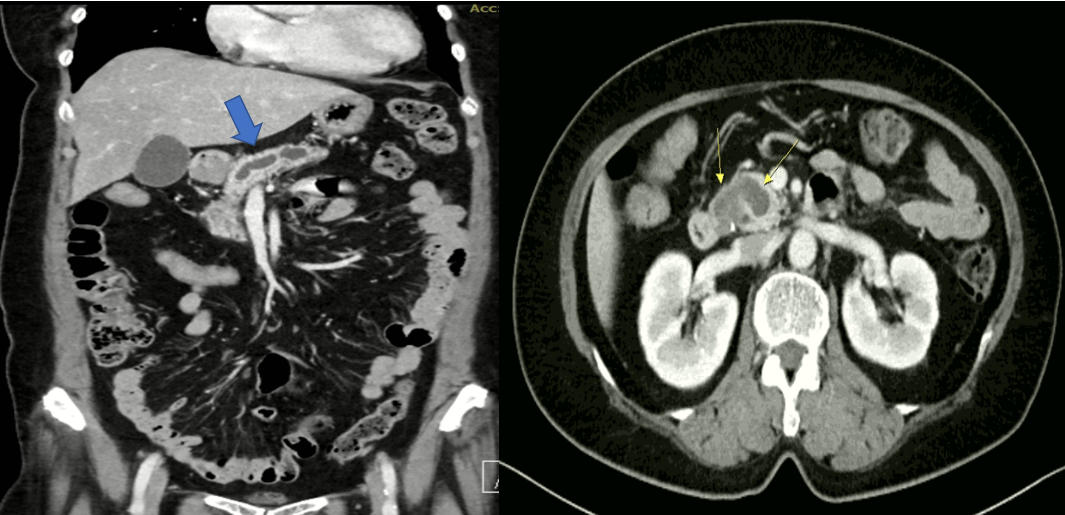

복부 CT에서 췌관의 확장이 관찰되며, 췌장의 머리 쪽에 약 2.5cm 크기의 물혹이 관찰되며 물혹 내부에 고형 물질이 의심되었습니다. (그림 3)

캡처_2025_01_01_14_31_00_809.png 그림 3. CT에서 췌관의 확장이 관찰되며 (파란 화살표), 췌장의 머리 쪽에 약 2.5cm 크기의 물혹이 있고 내부에 고형의 물질이 의심됨.(노란 화살표)